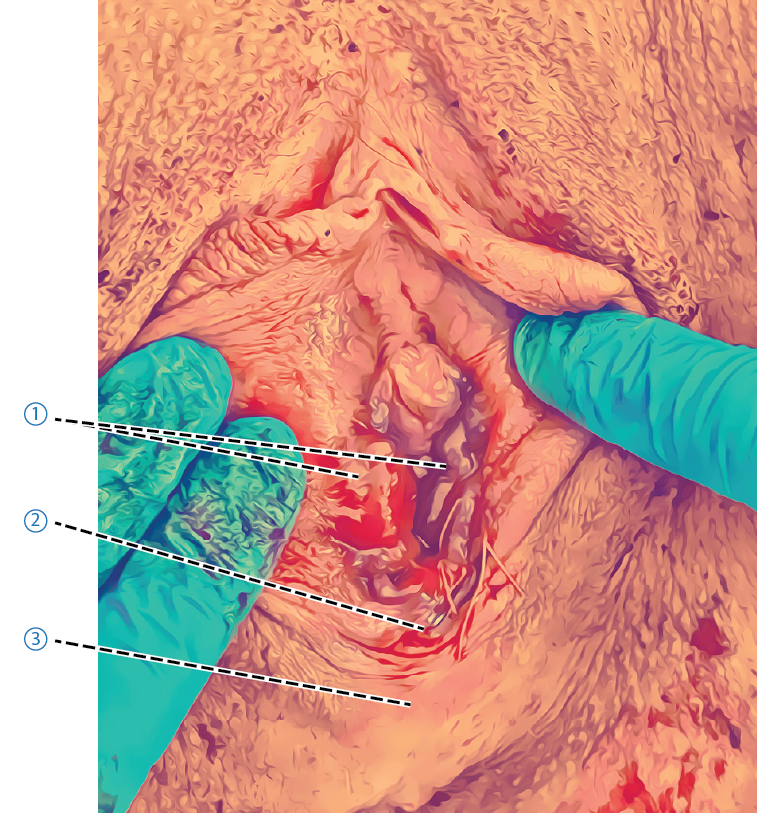

Adaptera muskelfästet för den ytliga delen av transversus perinei i medellinjen närmast den externa sfinktern. Ofta följer m bulbocavernosus med i denna sutur, om den inte följt med i suturen kan den vid behov sutureras ner mot m transversus perinei. Nedan visas bild på m bulbocavernosus som fäster mot ytliga delen av transversus perinei och därmed inte behövde sutureras (Figur A). Figur B visar m bulbocavernosus som släppt från m transversus perinei superficialis lateralt om mittlinjen.- Ytliga muskelfästet för M Transversus Perinei

- Hållsutur

- Rift i slemhinnan på labias insida

- Hymen

- Intakt muskelfäste för m. Bulbocavernosus

- Ytliga muskelfästet för M Transversus Perinei

Figur A.